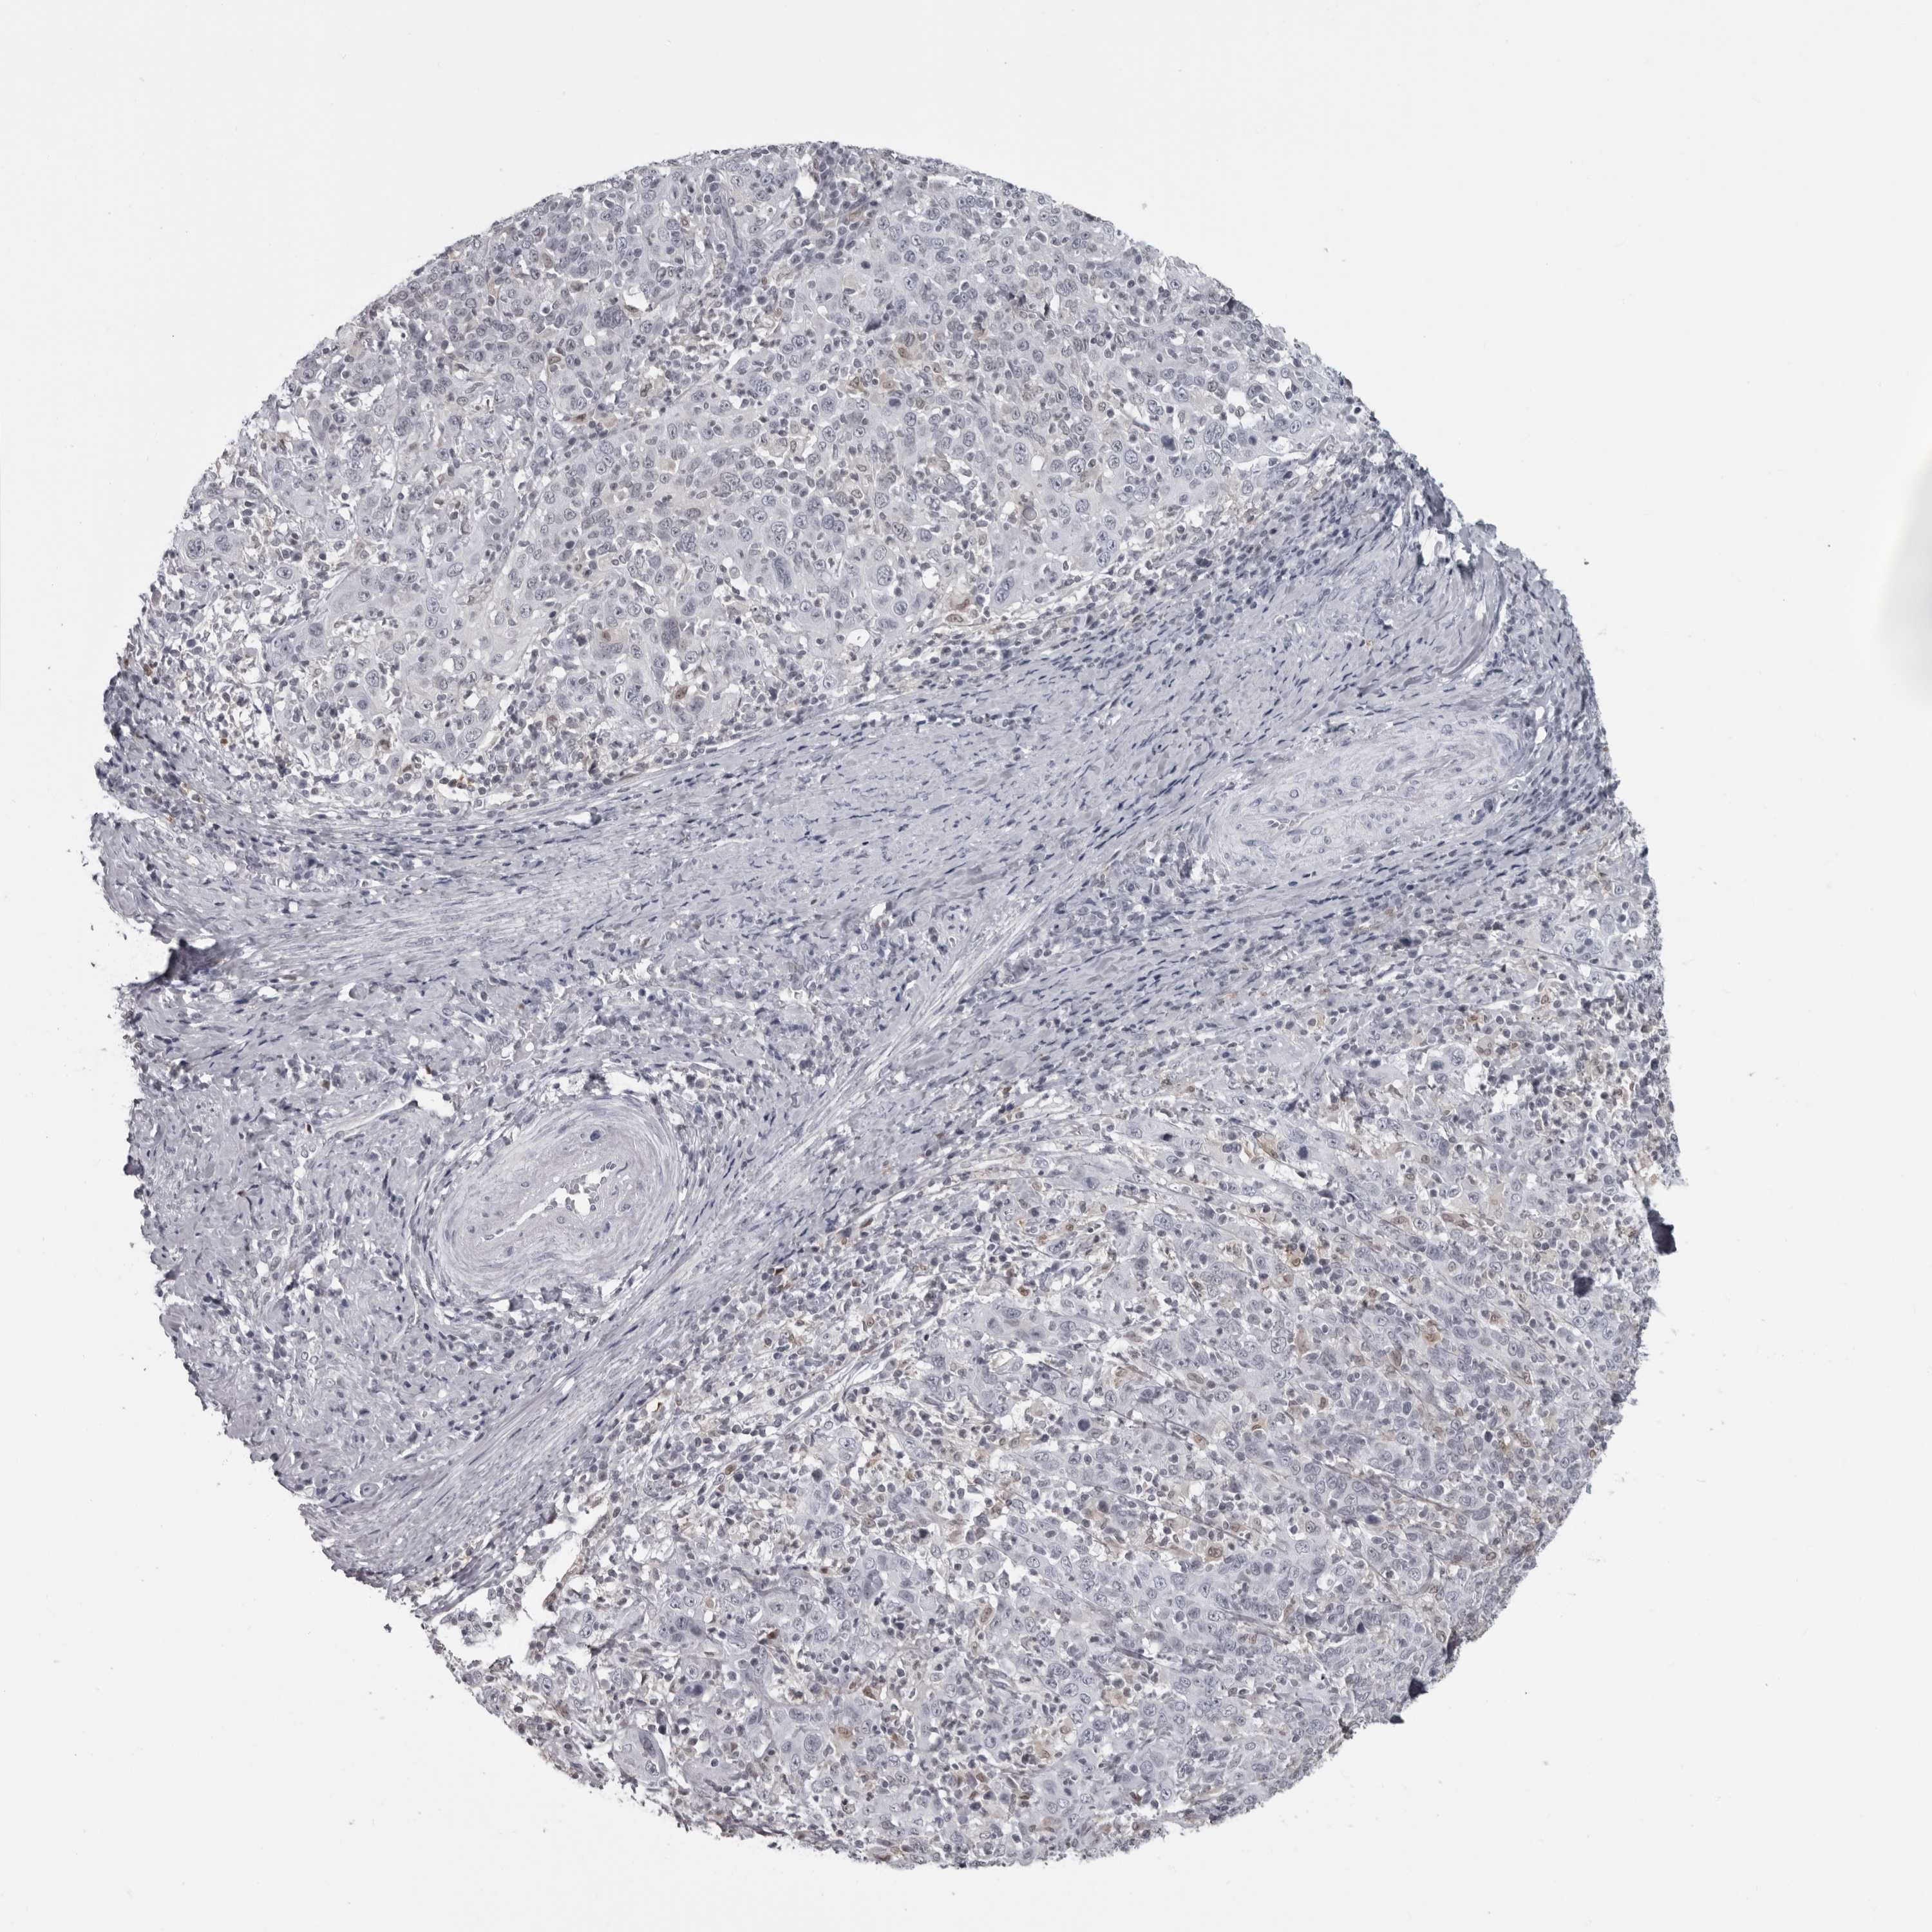

CERVICAL CANCER - Protein expressioni

A mouse-over function shows sample information and annotation data. Click on an image to view it in a full screen mode. Samples can be filtered based on level of antibody staining by selecting one or several of the following categories: high, medium, low and not detected. The assay and annotation is described here.

Note that samples used for immunohistochemistry by the Human Protein Atlas do not correspond to samples in the TCGA dataset.

Antibody stainingi

Antibody staining in the annotated cell types in the current human tissue is reported as not detected, low, medium, or high, based on conventional immunohistochemistry profiling in selected tissues. This score is based on the combination of the staining intensity and fraction of stained cells.

Each image is clickable and will lead to virtual microscopy that enables deeper exploration of all samples and also displays staining intensity scores, fraction scores and subcellular localization as well as patient and tissue information for each sample.

Antibody HPA028184

Staining

High

Medium

Low

Not detected

Intensity

Strong

Moderate

Weak

Negative

Quantity

>75%

75%-25%

<25%

None

Location

Nuclear

Cytoplasmic/membranous

Cytoplasmic/membranous,nuclear

Squamous cell carcinoma, NOS

Adenocarcinoma, NOS